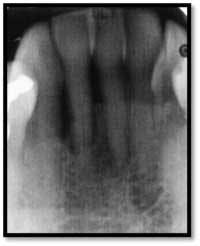

Severe bone loss #26, 8mm DF, 5mm straight facial, +2 mobility

A full set of radiographs taken 13 months post therapy show bone fill in the deepest pockets, with generalized pocket reductions of up to 7mm.